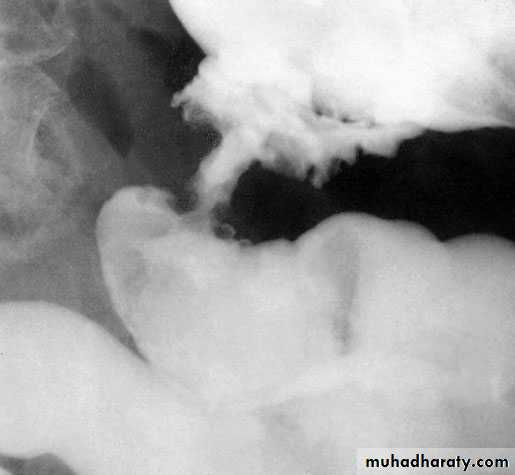

RadiologyDouble-contrast barium enema is used when colonoscopy is contraindicated.it shows a cancer of the colon as a constant irregular filling defect.Ultrasonography is often used as a screening investigation forliver metastases over the size of 1.5 cm, and CT is used in patientswith large palpable abdominal masses, to determine local invasion,and is particularly used in the pelvis in the assessment ofrectal cancer.

Apple core appearance